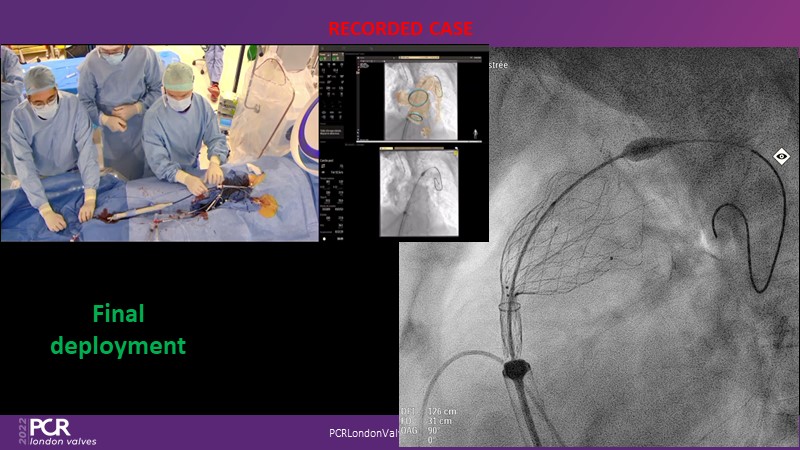

In this session from PCR London Valves 2022, discover the new Venus MedTech technology for tricuspid and pulmonary valve replacement, and a review of the clinical indications, selection criteria and procedural details.

- To learn about Venus MedTech technology, clinical indications and procedural details of valve replacement systems

- To learn more about the clinical experience and outcomes with Cardiovalve tricuspid and Venus P-valve